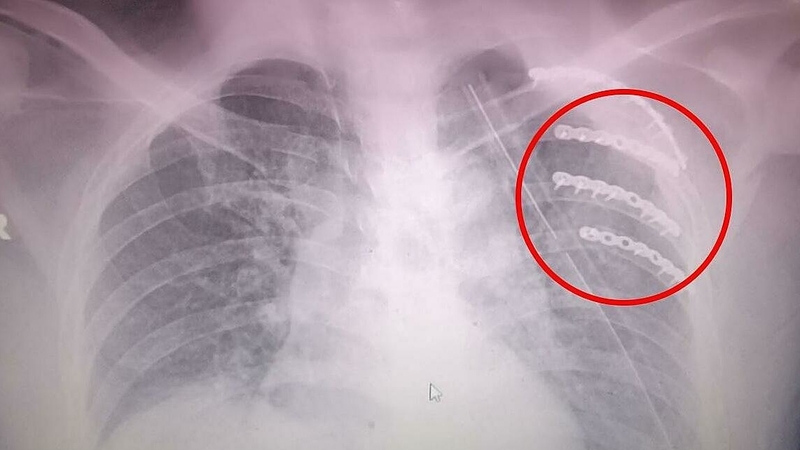

Trong quá trình điều trị gãy xương sườn, phương pháp chủ yếu là sử dụng các loại thuốc giảm đau và hỗ trợ dinh dưỡng để giúp vết thương mau lành. Hiện nay, việc sử dụng nẹp hoặc băng cố định không còn được khuyến khích trong điều trị gãy xương sườn.